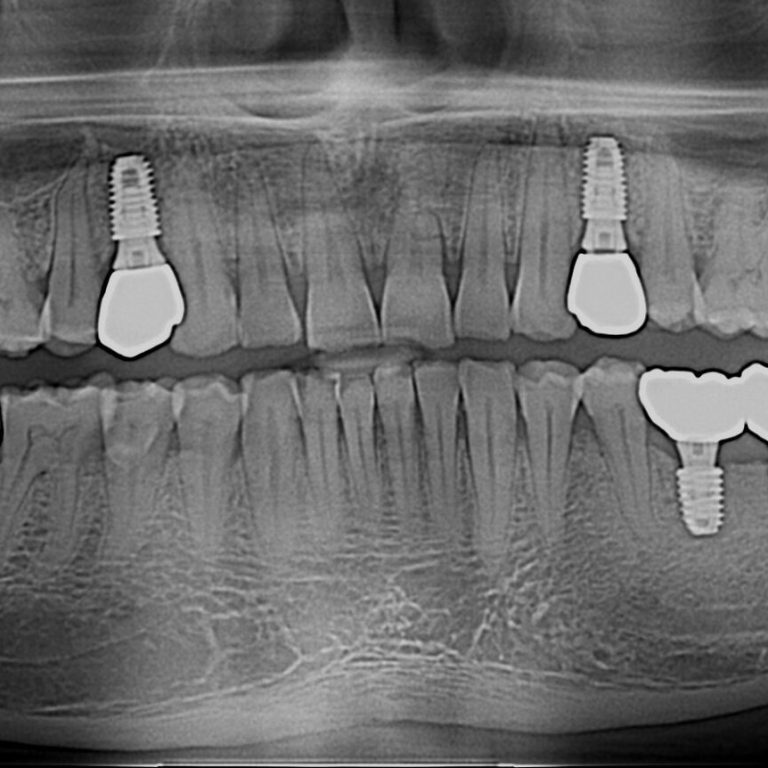

What Is a Dental Implant? A dental implant is a small titanium post that is surgically placed into …

If you have one or more missing teeth, a dental implant is the most reliable and long-lasting solution …

Dental Implant is the most popular way to replace missing teeth. Placing dental dental implant is pleasant surprise …